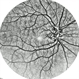

- pediatic retina, vascular anomaly

- Maria A. Martinez-Castellanos. Asociacion para Evitar la Ceguera en Mexico

- Imaging device

- RetCam II

- Fundus photograph of a 3-year-old boy with low vision, esotropia and leukocoria.